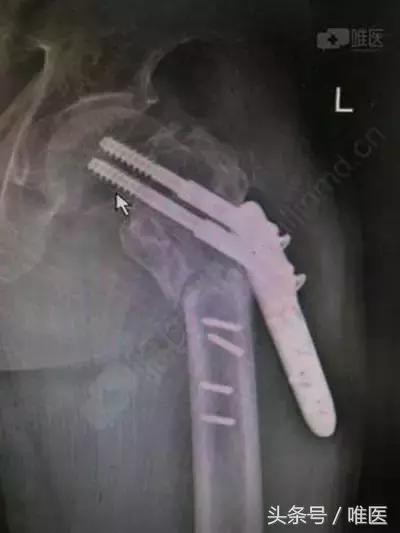

对于粗隆间骨折现在更多的采用髓内PFNA固定,生物力学上较髓外钉板固定更有优势。下面病例为粗隆间骨折PCCP钢板内固定6个月,钢板、螺钉断裂松动。X片提示粗隆下骨不连,考虑为骨不连所致钢板、螺钉金属疲劳断裂。对于粗隆部骨折骨不连所致的钢板断裂翻修,选择髓内固定or髓外固定?还是换髋?

粗隆间骨折钢板内固定6个月钢板断裂,疼痛不能行走3天。

当时受伤采用国产pccp钢板内固定,初期复位还可以,没有髋内翻,小转子掉了一块。

术前影像